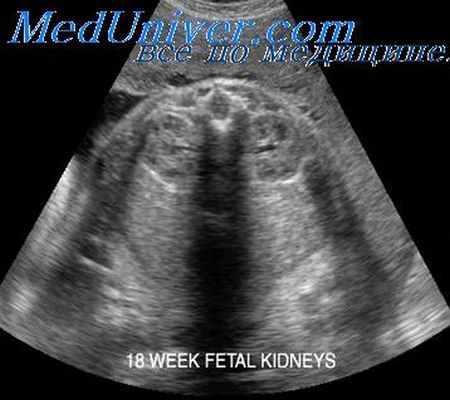

Остановка в развитии мочеточникового зачатка приводит к агенезии почки, которая может быть как односторонней, так и двухсторонней. Частота односторонней агенезии составляет примерно 0,3 на 1000 родов и сопровождается обычно весьма благоприятным прогнозом для плода. При пренатальном ультразвуковом обследовании в этом случае на пораженной стороне в почечной ямке не обнаруживается почки, а на другой стороне она имеет увеличенные размеры по сравнению с нормальными для данного срока беременности.

Важным аспектом является оценка надпочечника на пораженной стороне, который может уплощаться по форме и ложно восприниматься как почка. Этой ошибки можно избежать, если учитывать, что у надпочечника не имеется центрального гиперэхогенного комплекса и при продольном сечении не будет обнаруживаться типичная бобовидная форма почки. Важно также исследовать область малого таза плода, чтобы убедиться, что почка действительно отсутствует, а не расположена эктопически.